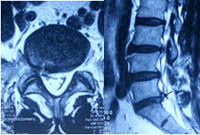

术前可见椎管内脱出的巨大髓核组织压迫神经(箭头所示) 术后3月复查MRI显示脱出的髓核组织消失,神经无明显受压